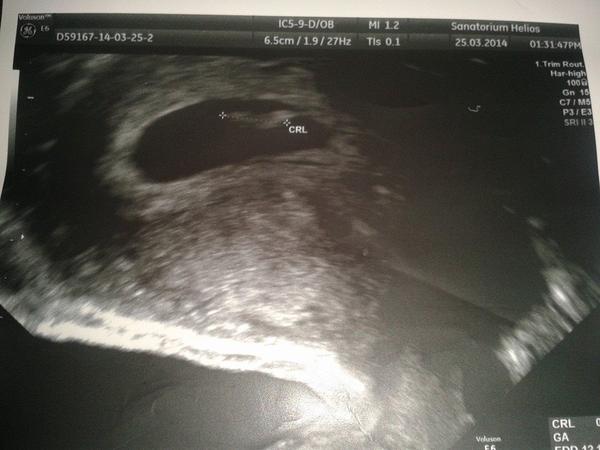

Mno tak na potřetí telefonát konečně měli výsledky a měla sem prej 470 hcg v patek a dneska už 1700 a zítra du na ultrazvuk tak doufam. že už tam něco uvidíme

Tak holky uz je tam gestacni vacek paty sesty tyden a za dva tydny se mame stavit na poslech srdicka

Tak holky dneska jjsem byyla si poslechnout srdicko bylo to uuuzasny mimisek ma uz 9mm a posle ovulace jsme teprve 6+6tt a za dva tydny dem znova zitra snad dodam fotky